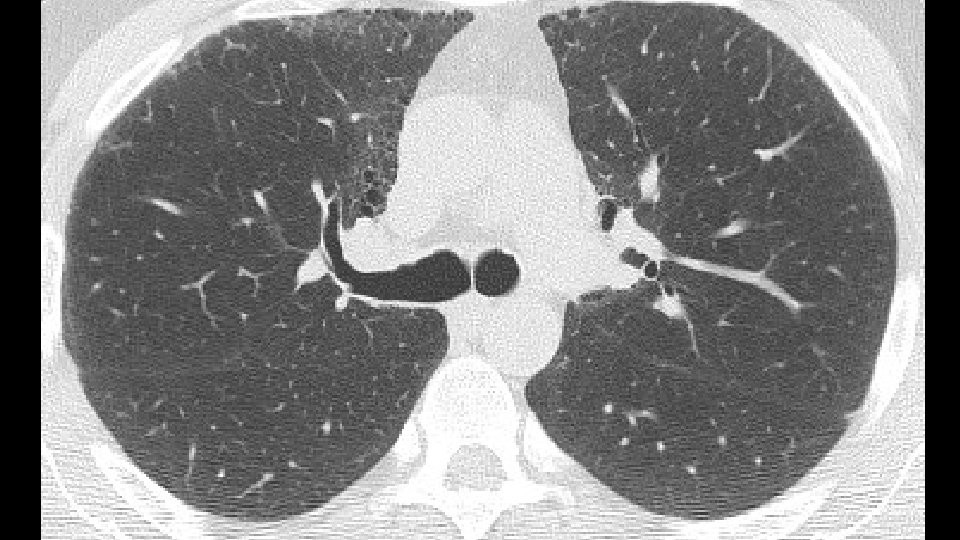

1. Mechanical stress and remodeling are highest in that areas in which traction bronchiectasis and honeycombing appear. Carloni A. et Al. Journal of theoretical biology 2013 2. Most of the "scarred" tissue is in the region distal to the traction bronchiectasis, beneath the pleura and does not concentrically surround the dilated bronchi. 2007 Score 1 bronchiectasis 2014 2010 Score 3 bronchiectasis Honeycombing

3. In Nonspecific Interstitial Pneumonia (NSIP), traction bronchiectasis are completely surrounded by the fibrotic tissue Fibrotic NSIPof the years NSIP in the course a 2009 b 2013